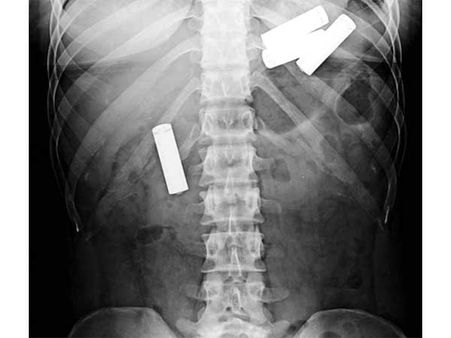

Drugs

A Nigerian man was caught at an airport in Malaysia while he was trying to export 52 capsules of methamphetamine. Wonder how would he get all these capsules out of his body! Phew.